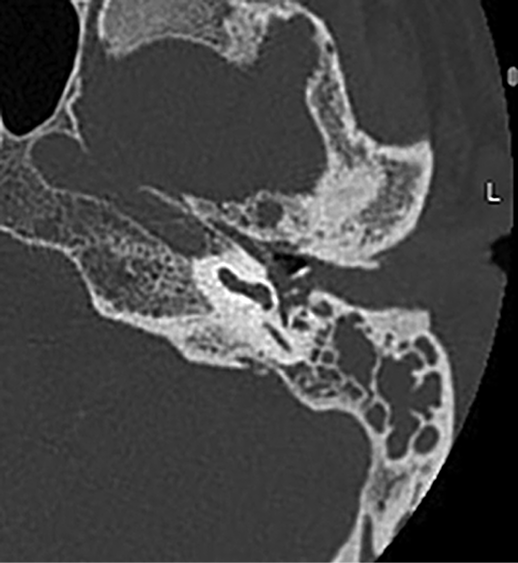

A 55-year-old man was referred to our hospital’s emergency department following one month of unsuccessful treatment at another facility. The patient presented with ear pain, hearing loss, and facial weakness, all localized to the left side. According to the patient, his symptoms had begun approximately a month earlier, prompting him to seek medical care. During the initial examination, swelling of the external auditory canal and purulent discharge were observed, obscuring the view of the eardrum. Local antibiotics and non-steroidal anti-inflammatory drugs were prescribed, but the symptoms persisted, leading the patient to seek further medical attention. It was then decided to hospitalize him and administer intravenous antibiotics. Despite continued hospital treatment, the symptoms persisted, and facial weakness developed on the left side. Given the ineffective response to intravenous antibiotics and the new onset of facial paresis, a computed tomography (CT) scan was conducted. The CT scan revealed opacified mastoid air cells and fluid in the tympanic cavity (Figure 1). Due to the patient’s deteriorating condition, he was referred to a tertiary hospital for consultation with an otorhinolaryngologist.

Figure 1. CT scan (axial view) of the temporal bone demonstrates opacification of the left mastoid air cells, tympanic cavity, and external auditory canal